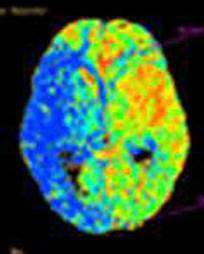

Рисунок 1- Компьютерная томография мозга.

Например, при исследовании перфузии компьютерный

кровоснабжения мозга (Рис. 1).